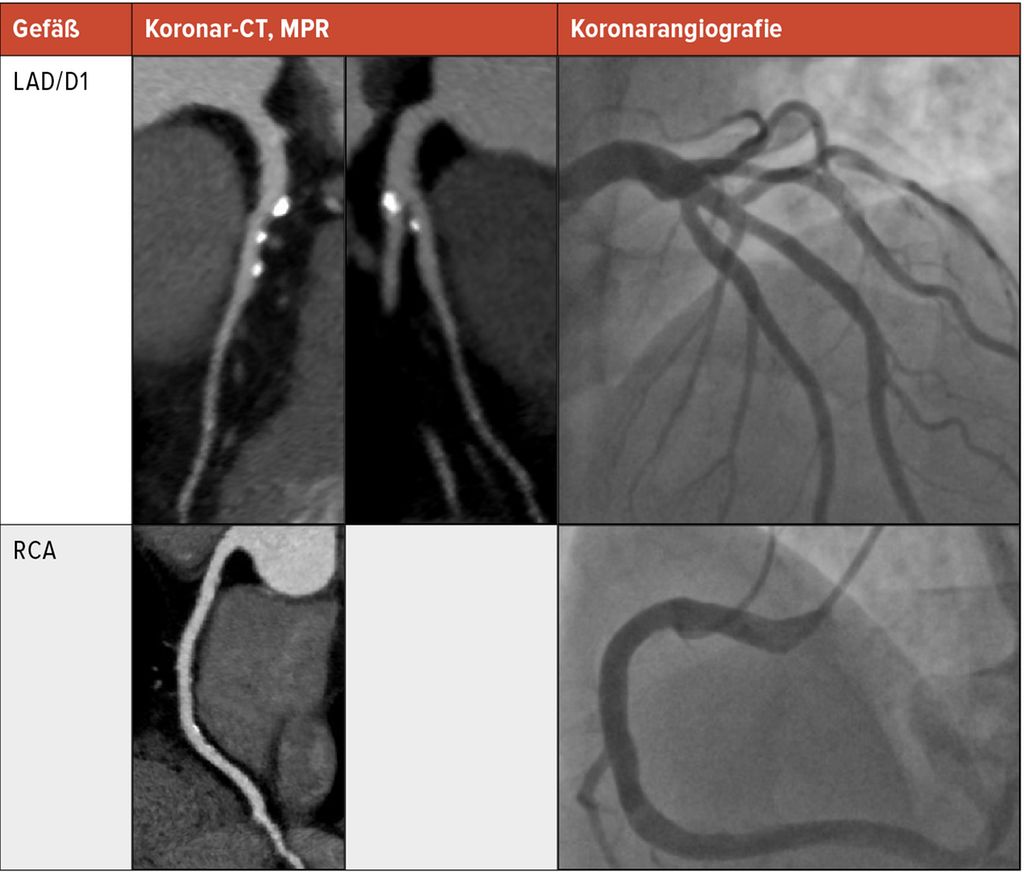

In Abbildung 1 sind multiplanare Rekonstruktionen (MPR) im Koronar-CT der invasiven Koronarangiografie gegenübergestellt.

Abb. 1: Multiplanare Rekonstruktionen (MPR) im Koronar-CT sind der invasiven Koronarangiografie gegenübergestellt. In der CT zeigten sich vor allem im Vorderwandbereich (left anterior descending [LAD] und großer erster Diagonalast [D1]) mehrere – großteils verkalkte – Plaques. Der Grad der Stenose wurde mit < 50% (somit CAD-RADS 3, P3 bei hoher Plaquelast) befundet. Dies deckte sich auch mit der Koronarangiografie, in der die Plaquelast jedoch weniger eindrücklich zur Geltung kommt. Im rechten Herzkranzgefäß (RCA) zeigten sich lediglich exzentrische Plaques ohne Lumeneinengung